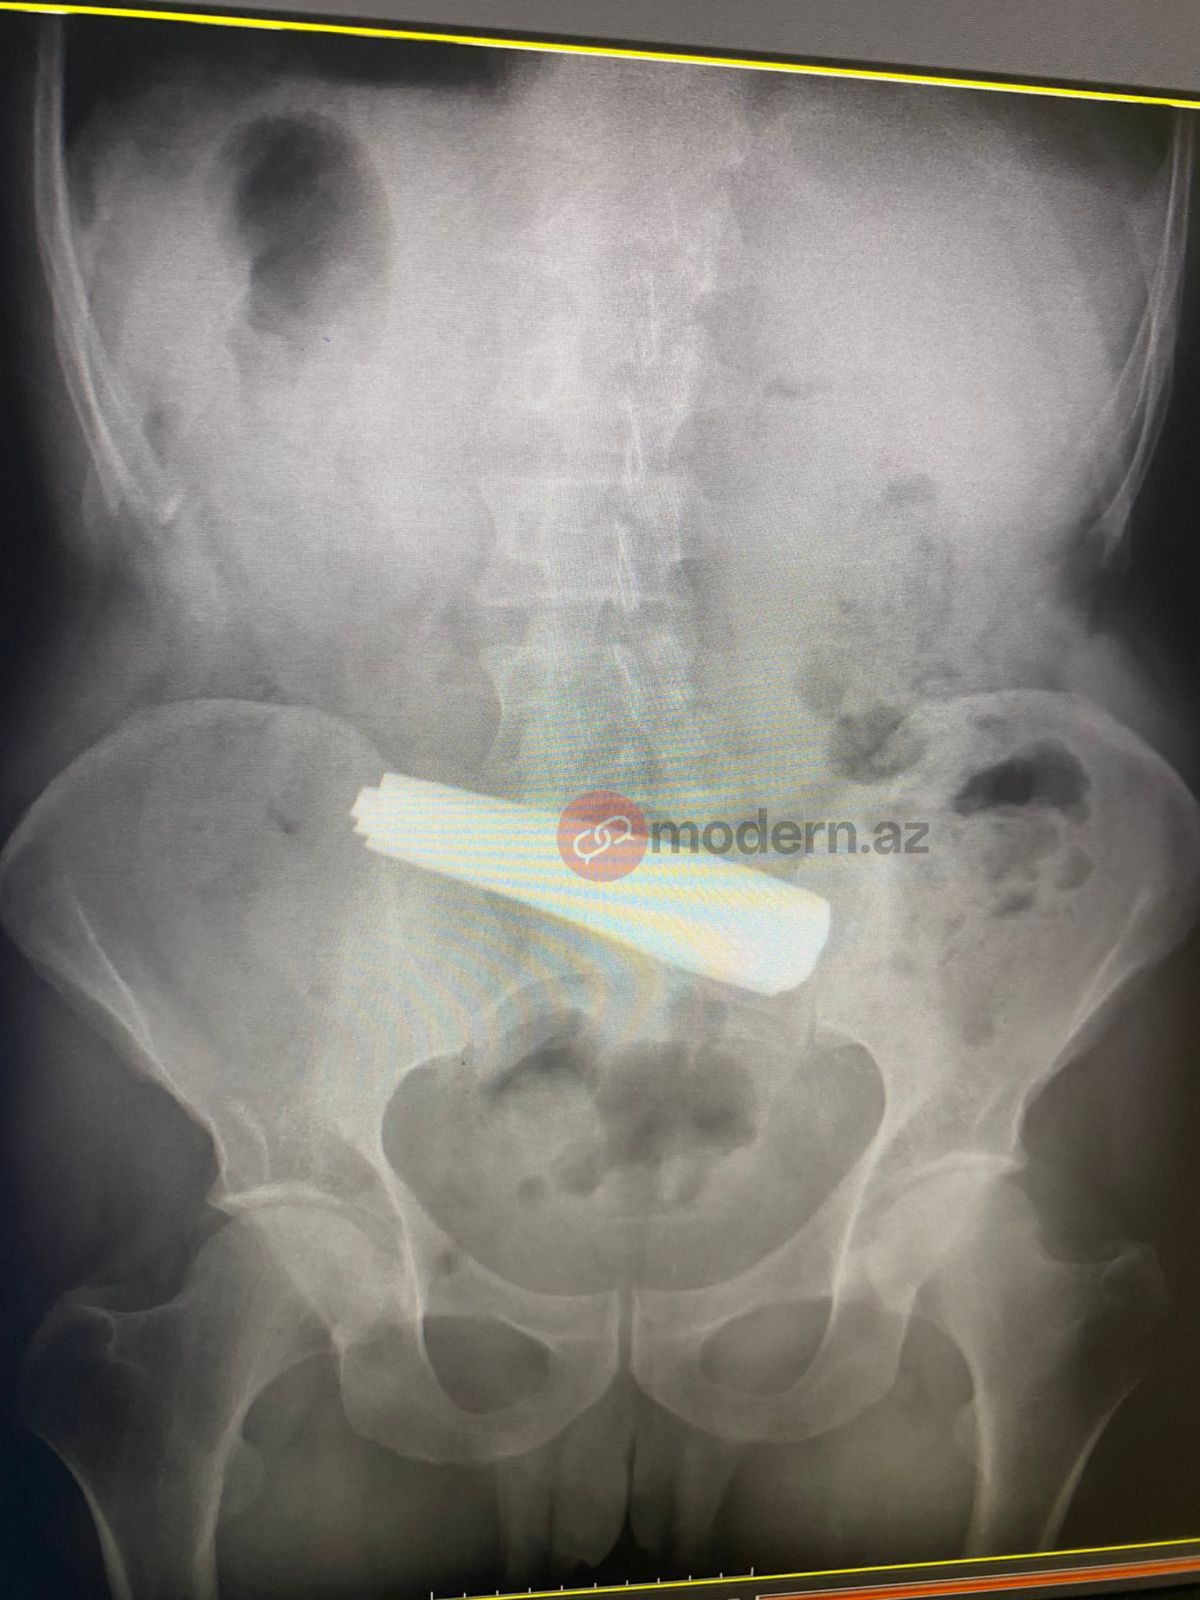

Bakıda bir nəfər 9 ədəd qaşıq udub.

Modern.az-a daxil olan məlumata görə, saat 01:00 radələrində 3 saylı şəhər klinik xəstəxanasınatəcili tibbi yardım üçün müraciət olunub.

İlkin məlumata görə, bir nəfərin bir neçə metal qaşıq udduğu bildirilib. Lakin xəstə bir neçə tibb müəssisəsi tərəfindən qəbul edilməyib.

Nəhayət, Bakı Sağlamlıq Mərkəzinə çatdırılan pasiyentə dərhal tibbi müdaxilə olunub. Məlumata görə, xəstə 9 ədəd metal qaşığı udub. Həkimlər tərəfindən həyata keçirilən əməliyyat uğurla başa çatıb.

Hazırda pasiyentin vəziyyəti stabildir və reanimasiya şöbəsində nəzarətdə saxlanılır.